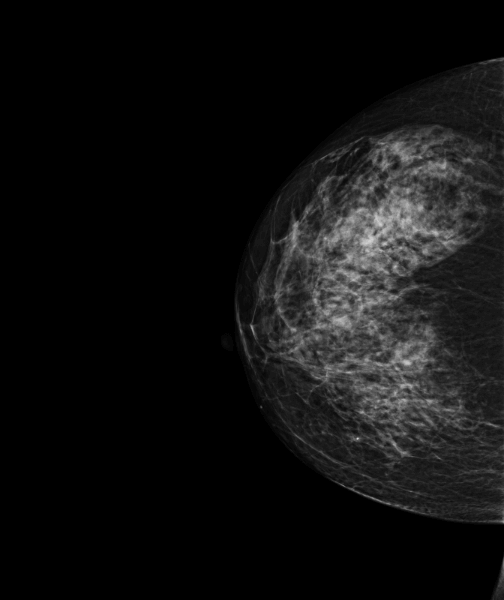

Femme de 53 ans, mammographie de dépistage.

MammoScreen™ pointe un surcroît d’opacité externe du sein droit.